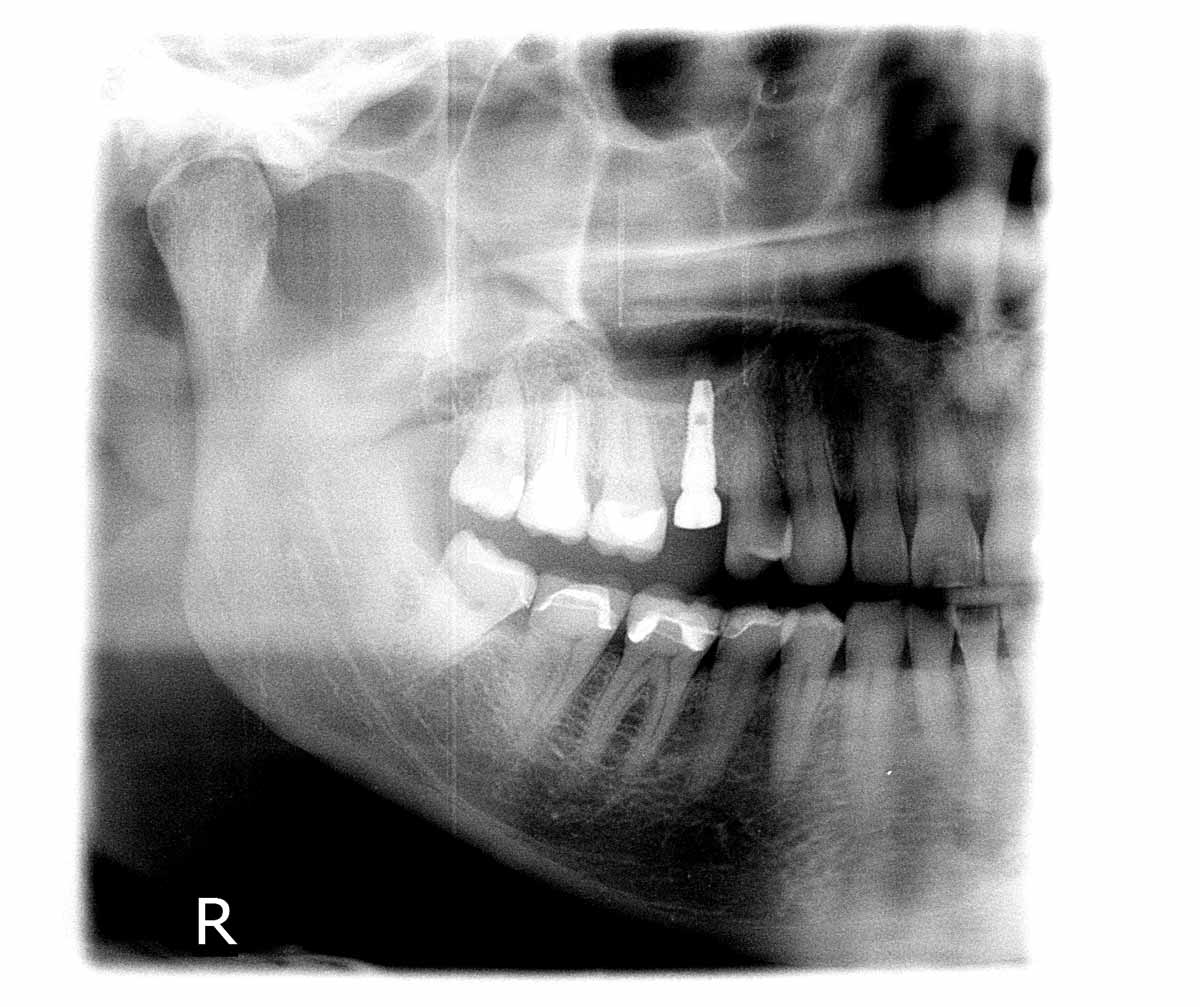

05/06 - Implant placement.Socket preservation with cerabone® - Dr. P. Kämmerer